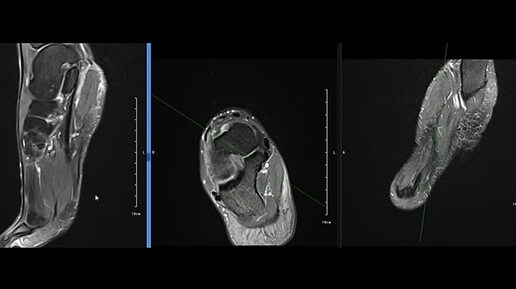

МРТ стопы